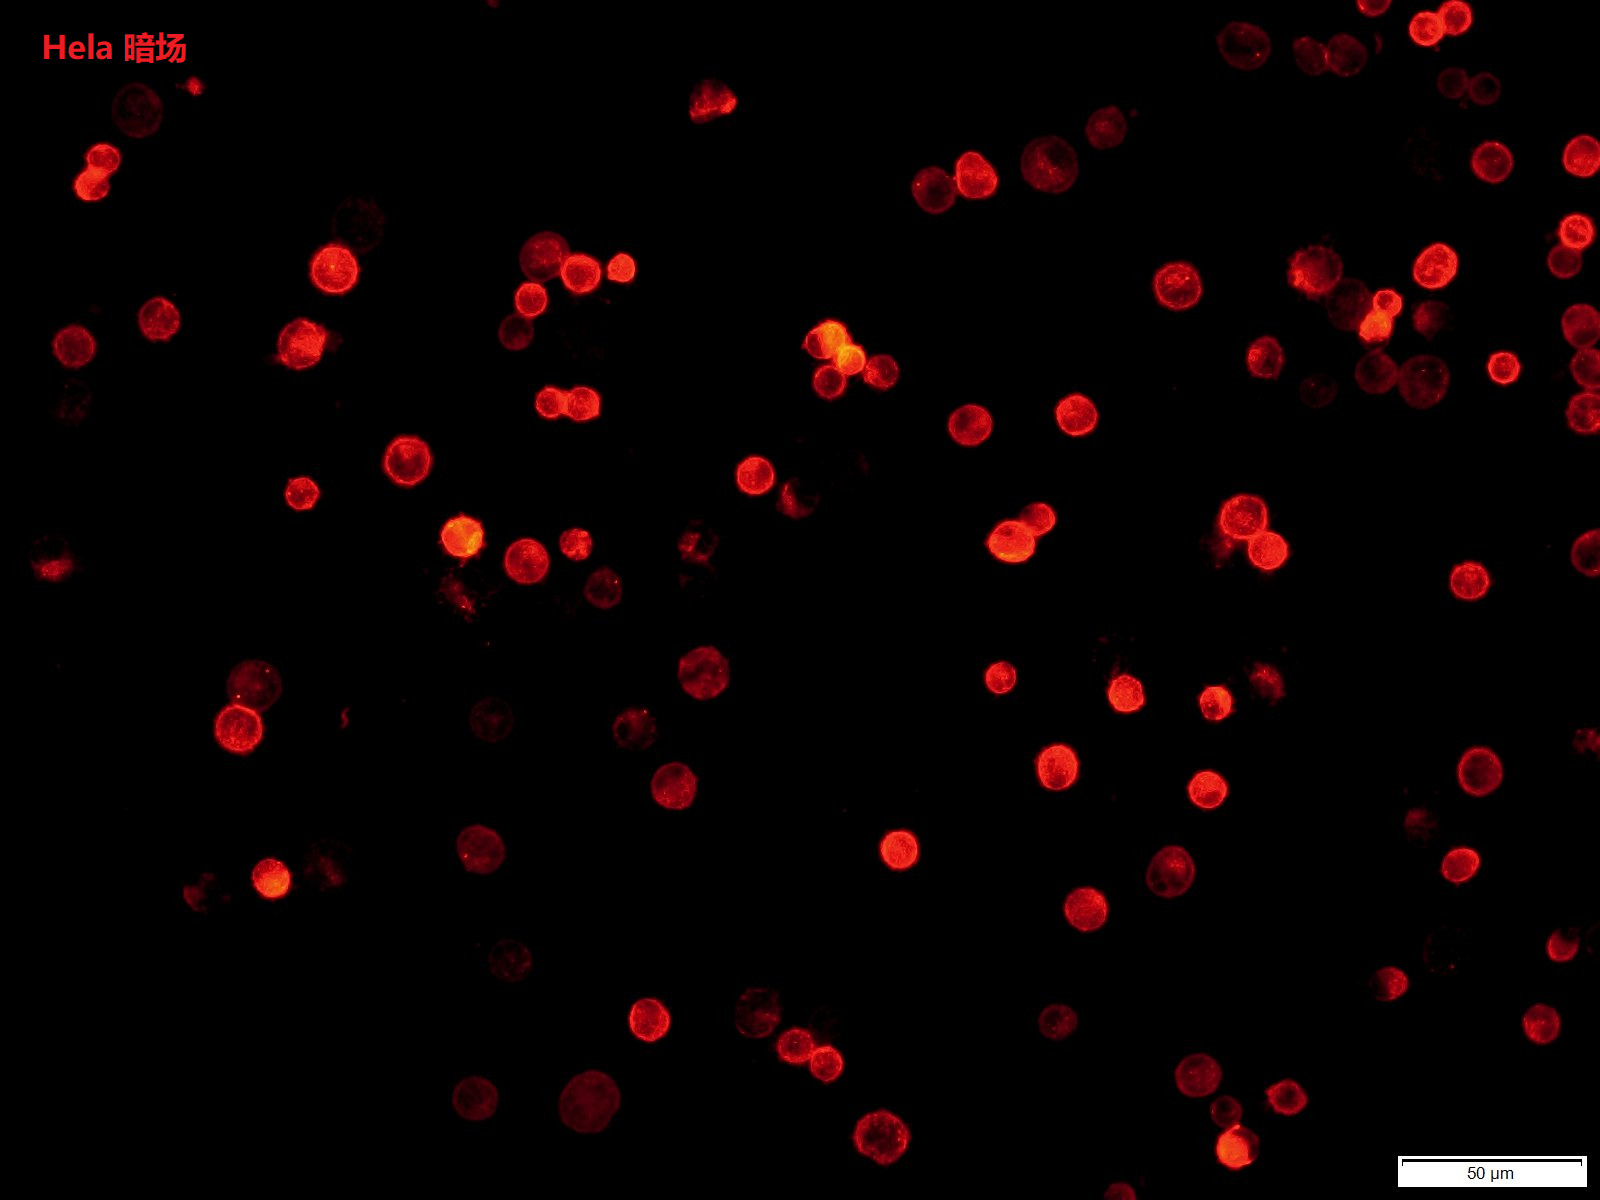

DiI即DiIC18(3),全称为1,1'-dioctadecyl-3,3,3',3'-tetramet.hylindocarbocyanine perchlorate,是最常用的细胞膜荧光探针之一,呈现橙红色荧光。DiI是一种亲脂性膜染料,进入细胞膜后可以侧向扩散逐渐使整个细胞的细胞膜被染色。

DiI在进入细胞膜之前荧光非常弱,仅当进入到细胞膜后才可以被激发出很强的荧光。DiI被激发后可以发出橙红色的荧光,DiI和磷酯双层膜结合后的激发光谱和发射光谱。其中,最大激发波长为549nm,最大发射波长为565nm。

实验参考图